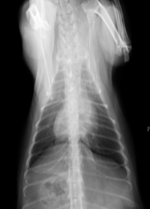

レントゲン検査にて、前胸部を大きく占める白い影が認められました。その部分を超音波にて確認したところ、心臓の前方に大きな腫瘤が確認できたので、針生検を行い、細胞診検査を行いました。br>

↑初回診察時の胸部レントゲン

細胞診の検査結果において、胸腺腫が疑われました。腫瘍のサイズがかなり大きかったため、外科手術の前に減容積を目的としたステロイドの内服薬による治療を開始しました。